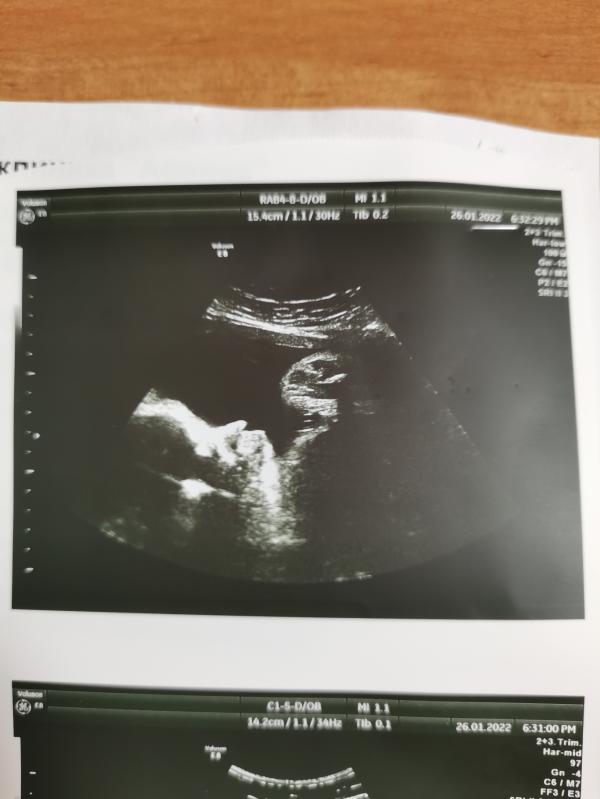

31,2н вес 1669гр😍 Совсем большой уже наш малыш 😘

У меня 30-31неделя ставили 1600(+ - 230 гр) ничего не говорили про то что маленький вес или на оборот большой.

В 31.1 1839 сказали , но не говорили что большая ) сказали стандарт ) родится около 3500 кг ) посмотрим как будет 🥰 они же сейчас очень быстро будут набирать 🥰

В 31 тоже были 1660. Родились в 35.4 2800. Вообще ничего не говорили,что ребенок маленький

У меня в 31 неделю вес малыша был 1600, подружки говорили , что такой маленький 😅 у них по 1800 -2000 кг

Мне на таком же сроке при весе 1600 +- 100 гр погрешности сказали маленькая 🤔 Вот поеду в пятницу ещё раз делать..